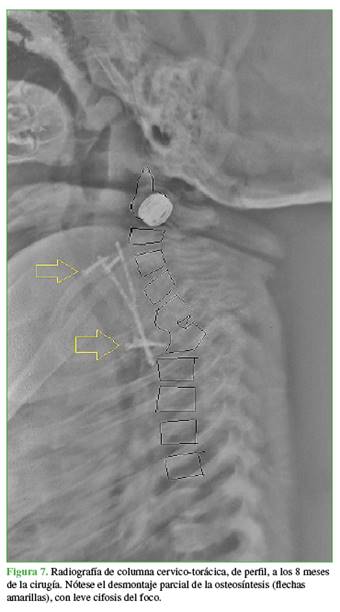

Sin embargo, a los 8 meses de la intervención, aunque el paciente no tenía síntomas, se observó un desmontaje de la osteosíntesis en los controles radiográficos, sin cifosis significativa, con desarrollo normal, sin signos ni síntomas neurológicos y aún con el uso continuo de la ortesis (Figura 7).

La instrumentación cervical y de columna torácica alta en niños, por lo general, no está exenta de complicaciones, sobre todo cuanto más pequeños son los niños.21 Si bien se ha utilizado con éxito en la columna torácica alta en niños <2 años,22 existen pocos reportes exitosos en menores de 1 año,3 y no hemos encontrado comunicaciones de uso de implantes por vía anterior en recién nacidos. En nuestro caso, el agregado de un implante de este tipo brindó mayor seguridad al constructo intraoperatorio (Figura 5) y, aunque hubo un desmontaje parcial (Figura 7), las placas permitieron mantener los injertos en su sitio hasta la consolidación del foco (Figura 8).

La complicación más frecuente de la enfermedad, fuera del déficit neurológico, es la disolución de los cuerpos vertebrales que lleva a una cifosis, muchas veces angular, asimilable a una cifosis congénita por aplasia de cuerpos vertebrales, y que requiere de cirugías reconstructivas generalmente por doble abordaje.1,23 Una vez curada la infección, si bien no hay muchos reportes a largo plazo con controles al final del crecimiento, esta deformidad por su gravedad y la corta edad de los pacientes con importante potencial de progresión, puede equipararse a la evolución de la cifosis pótica pediátrica24 y se pueden utilizar los mismos criterios para decidir sobre procedimientos adicionales. En nuestro caso, la deformidad residual que puede avanzar, con el consiguiente riesgo de deterioro neurológico por su ubicación (unión cervico-torácica y columna torácica alta)25 y el déficit ostensible de crecimiento de la parte anterior del segmento afectado (secundario a la destrucción de los cuerpos vertebrales y sus fisis), nos llevan a programar una segunda intervención (Figura 8).